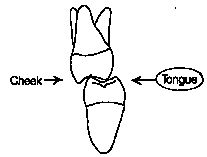

ABSTRACT The concept of immediate implant occlusal loading root form implants for fixed restorations has received increasing interest over the last five years. Studies have discussed the factors that may influence results, including implant number, implant length, bone density, occlusal schemes and patient habits. To reduce the risks, implant numbers should be increased, occusal forces … Read more